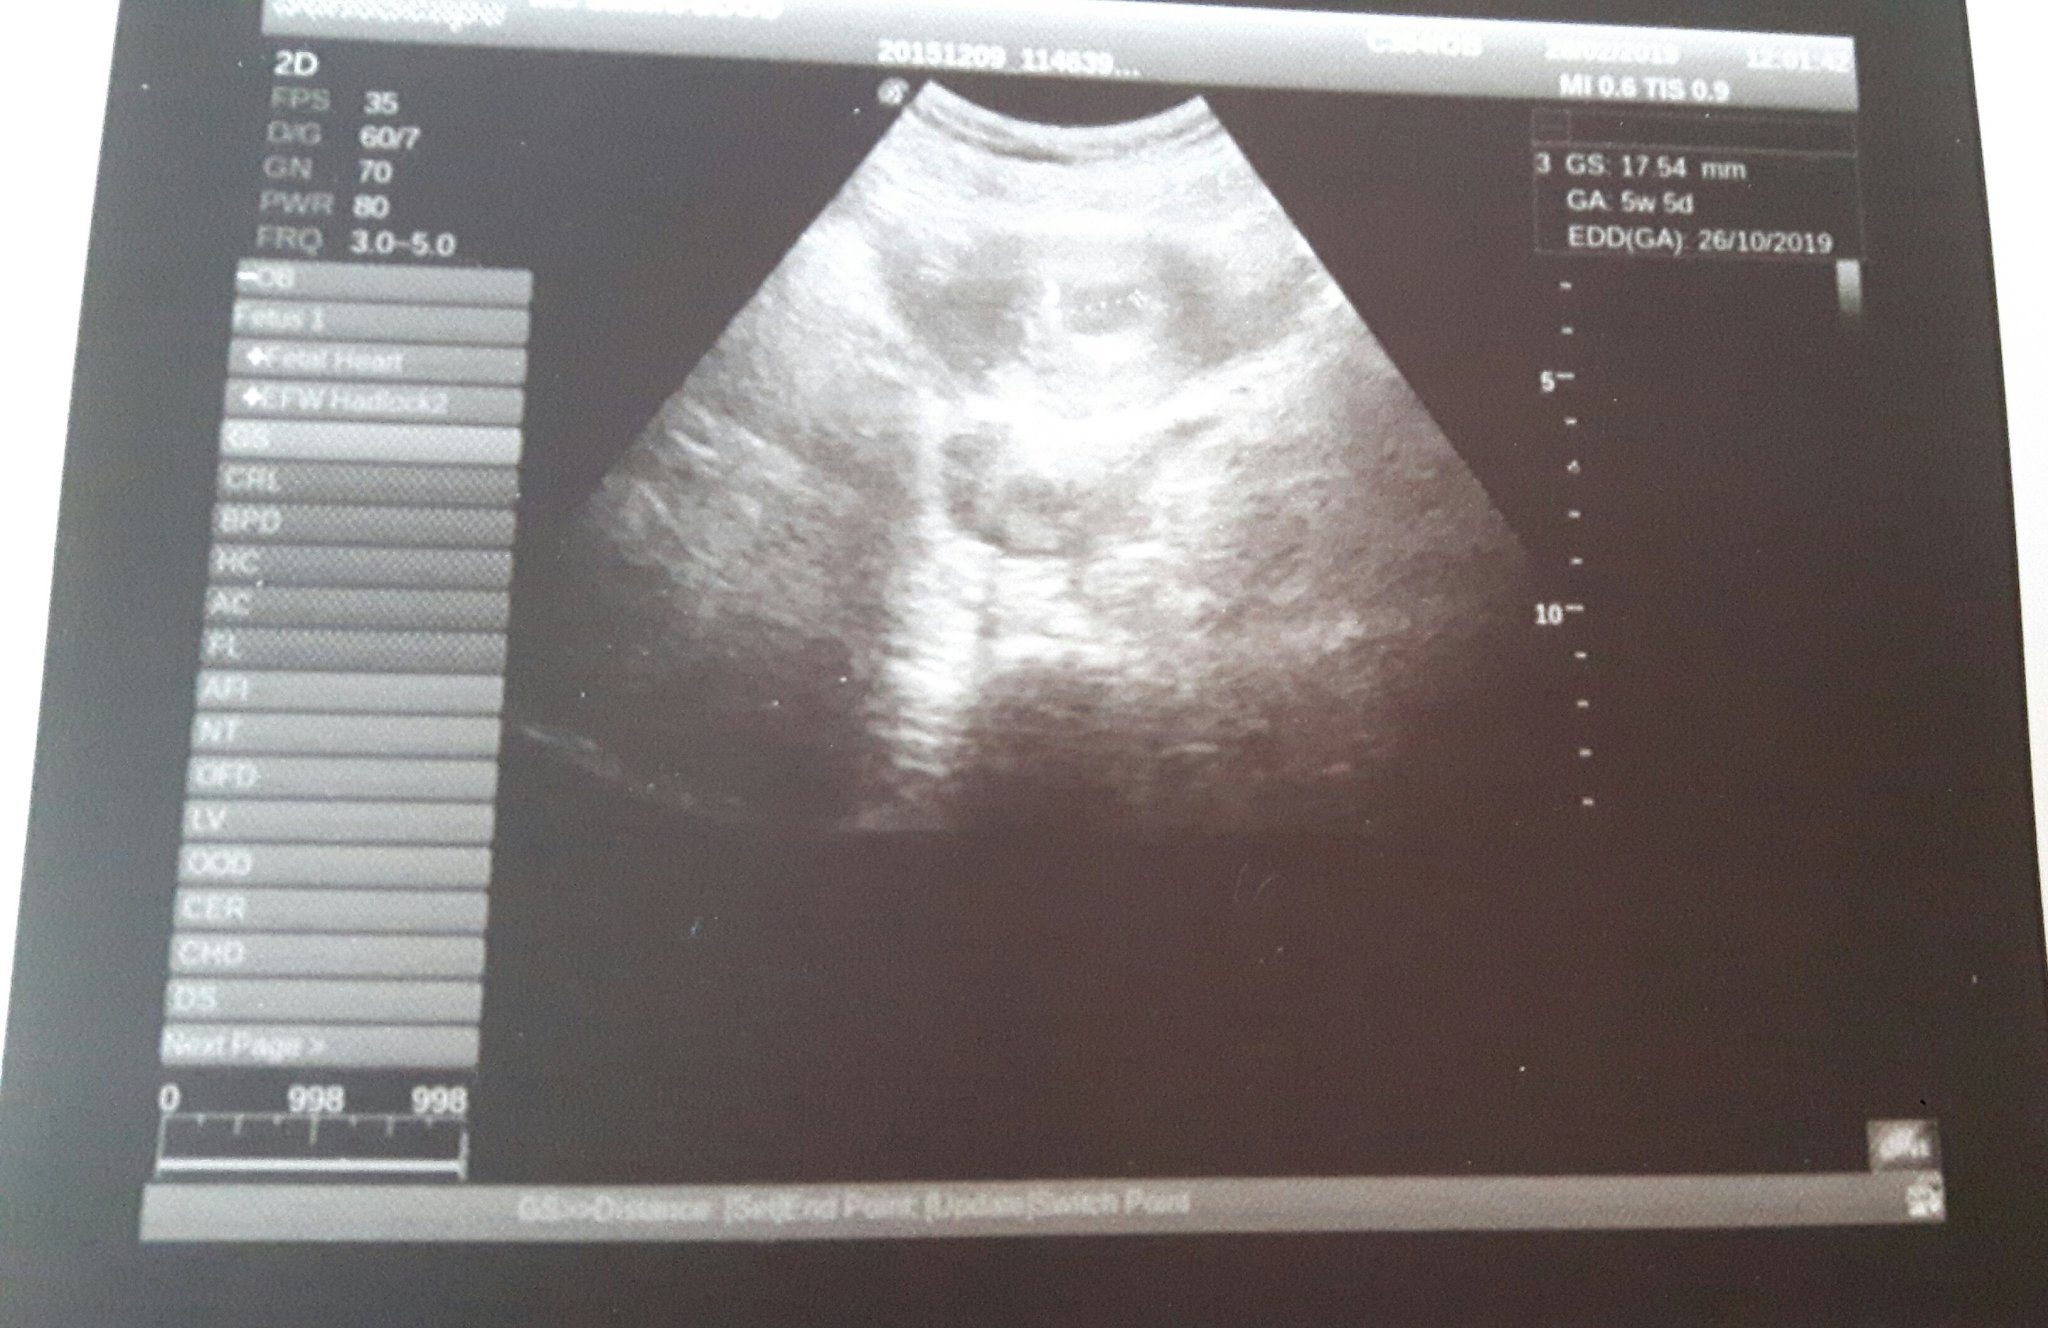

Здравейте, момичета! На 28г. съм от гр. Силистра. От около седмица наблюдавам темичката ви и вече се престраших да се включа. Много тихо и с голяма надежда ви споделям, че май ще съм с термин на 24.10 според приложението и 26.10, според доктора ,при който ходих днес. Това малко чудо е дълго чакано, 1г е работено усърдно за случването му. След 1 лапароскопия и 1 инжекция хориомон и няколко месечен прием на инофолик и сиофор,  както и дуфастон абсолютно всеки месец. Днес установиха, че съм 5г.с и 5д., видя се само сакче, лекаря каза, че е обнадежден, че започва струпване на клетки и до 10тина дни ще се види и ембрионче.  Днес отидох на лекар, защото от 2 дни придърпването ниско долу в корема спря и гърдите ми също се поуспокоиха  (знам, че може и да е неприятна новина, може и да не е...). Лекарят, който ще наблюдава бременността ми (Б.  Бойчев от гр. Тутракан), ми назначи час за 11.03 каза, че няма смисъл по-рано, но според мен има най-малкото да се види дали е извънматочна, та днес при този който ходих, в гр. Силистра, техниката ми се видя доста елементарна, а като знам как миналия август ми обърка жълто тяло с киста (моя док. Каза че това е честа грешка, но все пак) и съм леко замислена тоя човек въобще видя ли нещо като хората? Просто съм притеснена, а часът ми е много далече....

Не мога да разчета снимката, но нещо е измерено и е вътрематочно, ( вероятно е или сакчето, или ембриончето), така че според мен за това не се тревожи...

Според мен със сигурност не е извънматочна то се вижда и от снимката, а относно симптомите не се притеснявай, аз нямам никакви, понякога ме преболяват много леко гърдите и после може да спрат за дни, чувствам се перфектно и при първата си бременост бях така, единственият ми симптом беше растящият корем😂